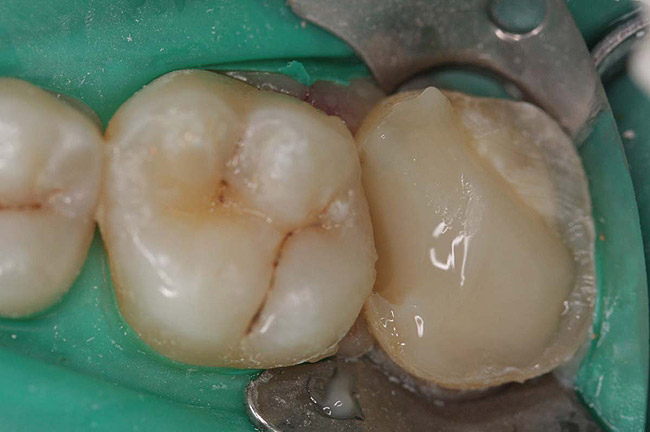

Case 2

A Class IIIN maxillary left second molar required restoration (Figure 6). Four canals, a chamber space, and little cross section of tooth structure were in the gingival third. Gutta-percha was removed with a Peeso reamer supplied in the C-1 kit. The canal was shaped with a bur in the kit, which was the same size as the corresponding post (Figure 7). The tooth structure was bonded with Brush & Bond™ (Parkell, www.parkell.com), and then the resin cement was spun into the canal with a lenticulo spiral. A C-1 white post was placed in the palatal canals (Figure 8). The C-1 White Post is a fiber-reinforced composite post, which flexes at the same rate as dentin to minimize root stresses.

Core build-up was completed with Absolute Dentin™ (Parkell, www.parkell.com) dual-cure high-strength core composite. There are variations on color and how materials cure. For example, Light-Core™ (Bisco, www.bisco.com) is a light-cured blue material, Encore® (Centrix, www.centrixdental.com) is a self-cure white material, and Para Core (Coltène Whaledent, www.coltene.com) is a dual-cure white or dentin-colored material. Material was placed directly and light-cured for 40 seconds (Figure 9). Final preparation for a PFM was completed (Figure 10). The final crown was placed (Figure 11).

Figure 6  Endodontically treated maxillary right second molar.

Figure 6

Figure 7  Second molar with the palatal canal prepared for post placement.

Figure 7

Figure 8  Second molar after post cementing.

Figure 8

Figure 9  Cure core material placed without a matrix.

Figure 9

Figure 10  Final tooth preparation to accept a PFM crown.

Figure 10